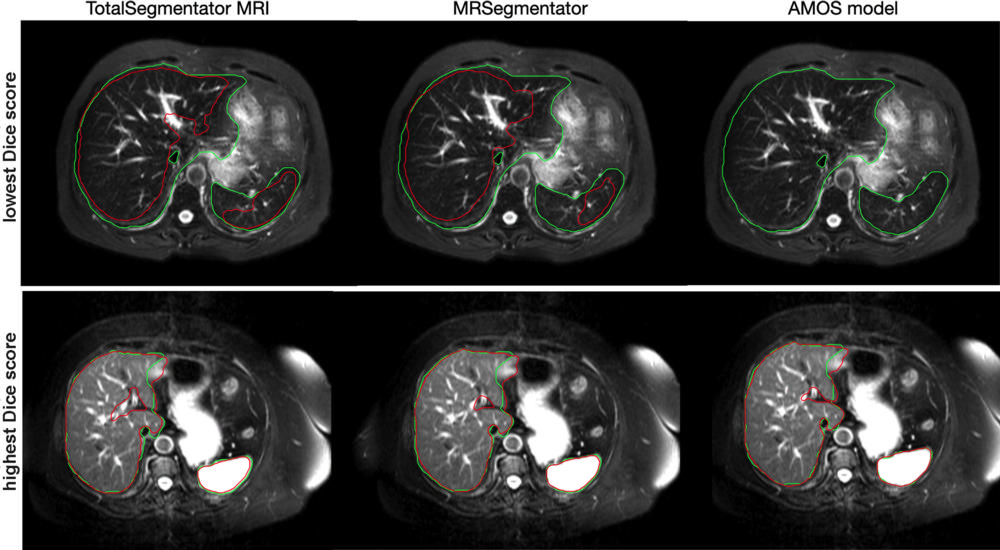

To evaluate the model’s performance, Dice scores—which measure how similar two sets of data are—were calculated between predicted segmentations and radiologist reference standards for segmentations. The model performed well across the 80 structures with a Dice score of 0.839 on an internal MRI test set. It also significantly outperformed two publicly available segmentation models (0.862 versus 0.838 and 0.560) and matched the performance of TotalSegmentator CT.

Figure 5. Axial MRI images from the cases with the lowest (top) and highest (bottom) Dice score in the CHAOS external test set for our proposed model, TotalSegmentator MRI, as well as for two publicly available baseline models, MRSegmentator and AMOS. The reference segmentation for liver and spleen is shown in green, and the segmentation of the model is shown in red. The CHAOS dataset was used to show the best and the worst results because this dataset is the most independent from the training data of the three models.